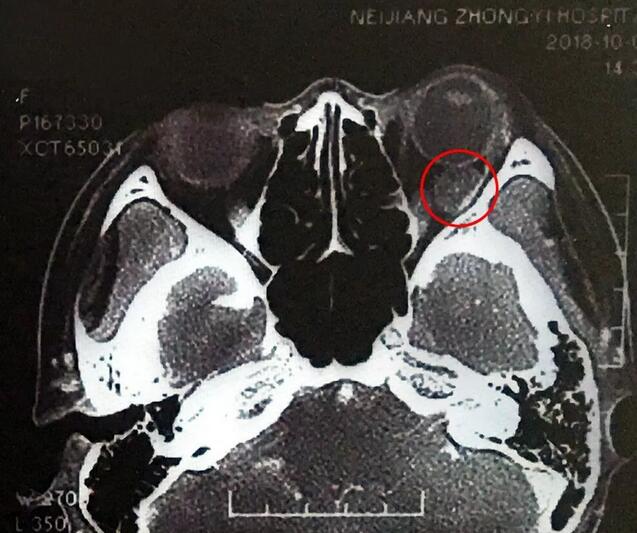

小何是四川南部县人,今年20岁,在内江上大学。今年9月底开始,出现头痛、反复呕吐,吐得连药都吃不下。医生建议小何做了脑部CT,“结果显示左眼眼球后部有个东西,经过进一步检查竟是肿瘤!”这对小何来讲真是个晴天霹雳。

在成都6686 - 看球聊球追世界杯就来6686体育有限公司官方网站,经过详细检查,罗清礼教授根据他40余年的丰富经验,判断为淋巴血管瘤。“现在,虽然她双眼的视力都是1.0,但是眼内肿瘤已经接近眼球那么大了,若不及时手术必将失明。”

罗教授介绍,淋巴血管瘤早期症状并不明显,“一般人感冒是不会头痛、呕吐的。小何的感冒非常幸运,她感冒后引起淋巴增生,导致肿瘤内出血,然后引起了头痛、呕吐等症状,让她能够尽早发现了肿瘤。”患者的肿瘤体积较大,位置较深,位于眶间且紧挨着视神经,手术稍有差错,就可能导致患者视力丧失、大出血等情况发生。得知手术风险后,患者和家属表示非常理解并信任罗教授,坚决要求手术医治。